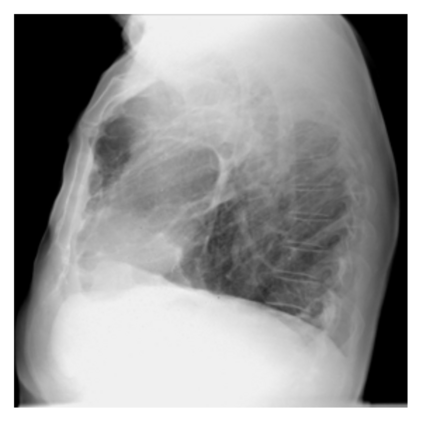

The evaluation of infectious disease processes on radiologic images is an important and challenging task in medical image analysis. Pulmonary infections can often be best imaged and evaluated through computed tomography (CT) scans, which are often not available in low-resource environments and difficult to obtain for critically ill patients. On the other hand, X-ray, a different type of imaging procedure, is inexpensive, often available at the bedside and more widely available, but offers a simpler, two dimensional image. We show that by relying on a model that learns to generate CT images from X-rays synthetically, we can improve the automatic disease classification accuracy and provide clinicians with a different look at the pulmonary disease process. Specifically, we investigate Tuberculosis (TB), a deadly bacterial infectious disease that predominantly affects the lungs, but also other organ systems. We show that relying on synthetically generated CT improves TB identification by 7.50% and distinguishes TB properties up to 12.16% better than the X-ray baseline.